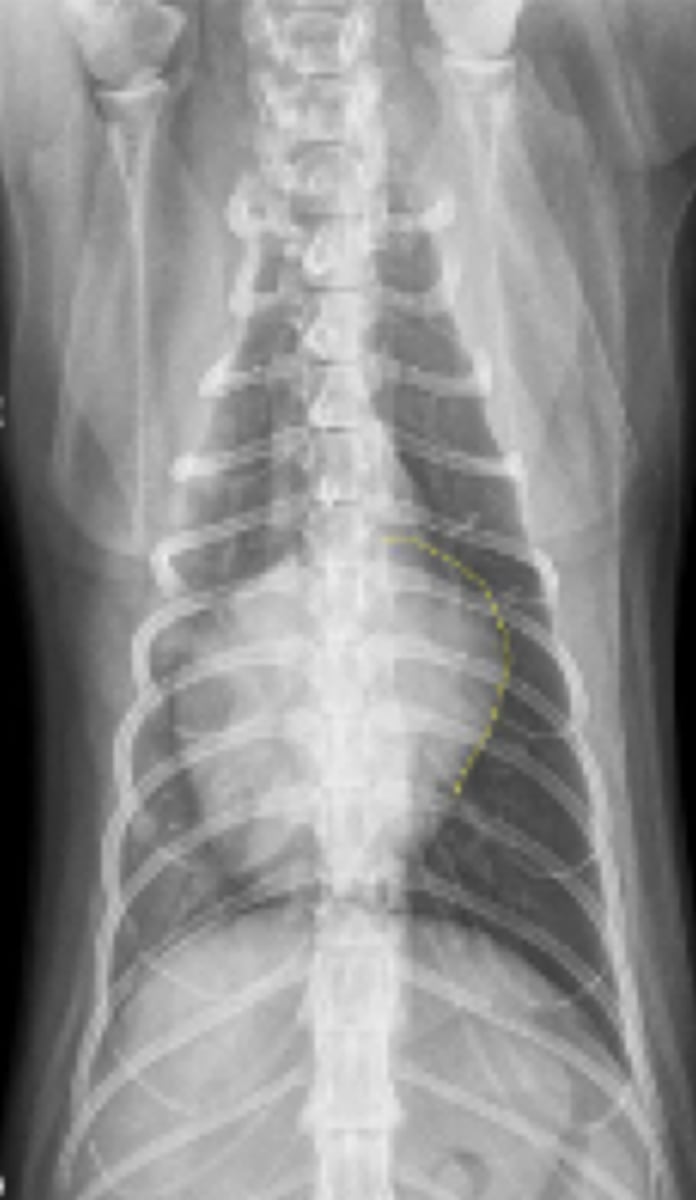

efusión pleural

patología: